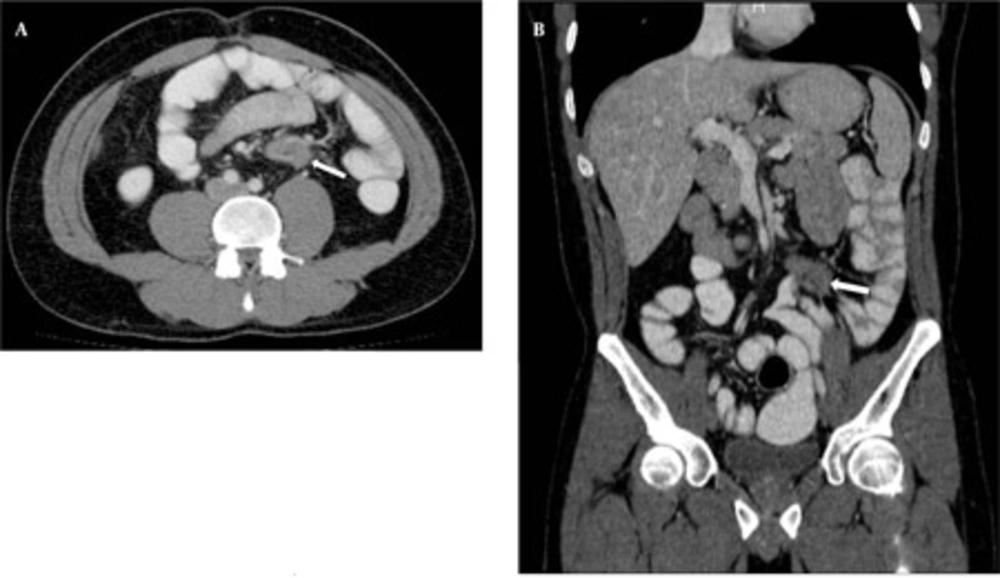

In CTE examination, there was no sign of manifested small bowel obstruction and intraluminal pathology. Intraabdominal solid organs were normal. A 39 × 42 × 36 mm sized contrast material enhancing solid mass was seen between the rectus muscles at the superior region of the umbilicus, invading to the subcutaneous fatty tissue anteriorly and limited by the omentum posteriorly. This mass had a well-defined margin making indentation without invasion to the small bowel loops (Figure 1). Another similar solid mass 60 × 48 × 35 mm in size was seen in the right inguinal region, anterolateral to the right rectus muscle, similarly indentated small bowel loops and limited by the omentum. Adjacent to the posterior segment of the eleventh left rib, a similar solid subcutaneous lesion (approximately 13 mm in diameter) was observed. In addition, another 38 × 33 × 29 mm sized, hyperdense mass with lobulated contour was seen at the small bowel mesentery, being close to the ileal branches of the superior mesenteric artery (SMA). It is observed that, this mass surrounded the SMA branches, but did not cause a significant obstruction in the arterial flow (Figure 2). Small bowel segments close to the defined mass were detected as normal. According to CTE results, this mass was interpreted as a mesenteric DT.

A, Axial; and B, Reformatted coronal CTE images of the patient. Morphology of mesenteric desmoid tumor (arrows) and the relationship between the tumor and the small bowel-mesenteric vasculature is seen on MDCT images. In addition, small bowel ischemia, invasion, obstruction or any other complication of desmoid tumors was not detected.